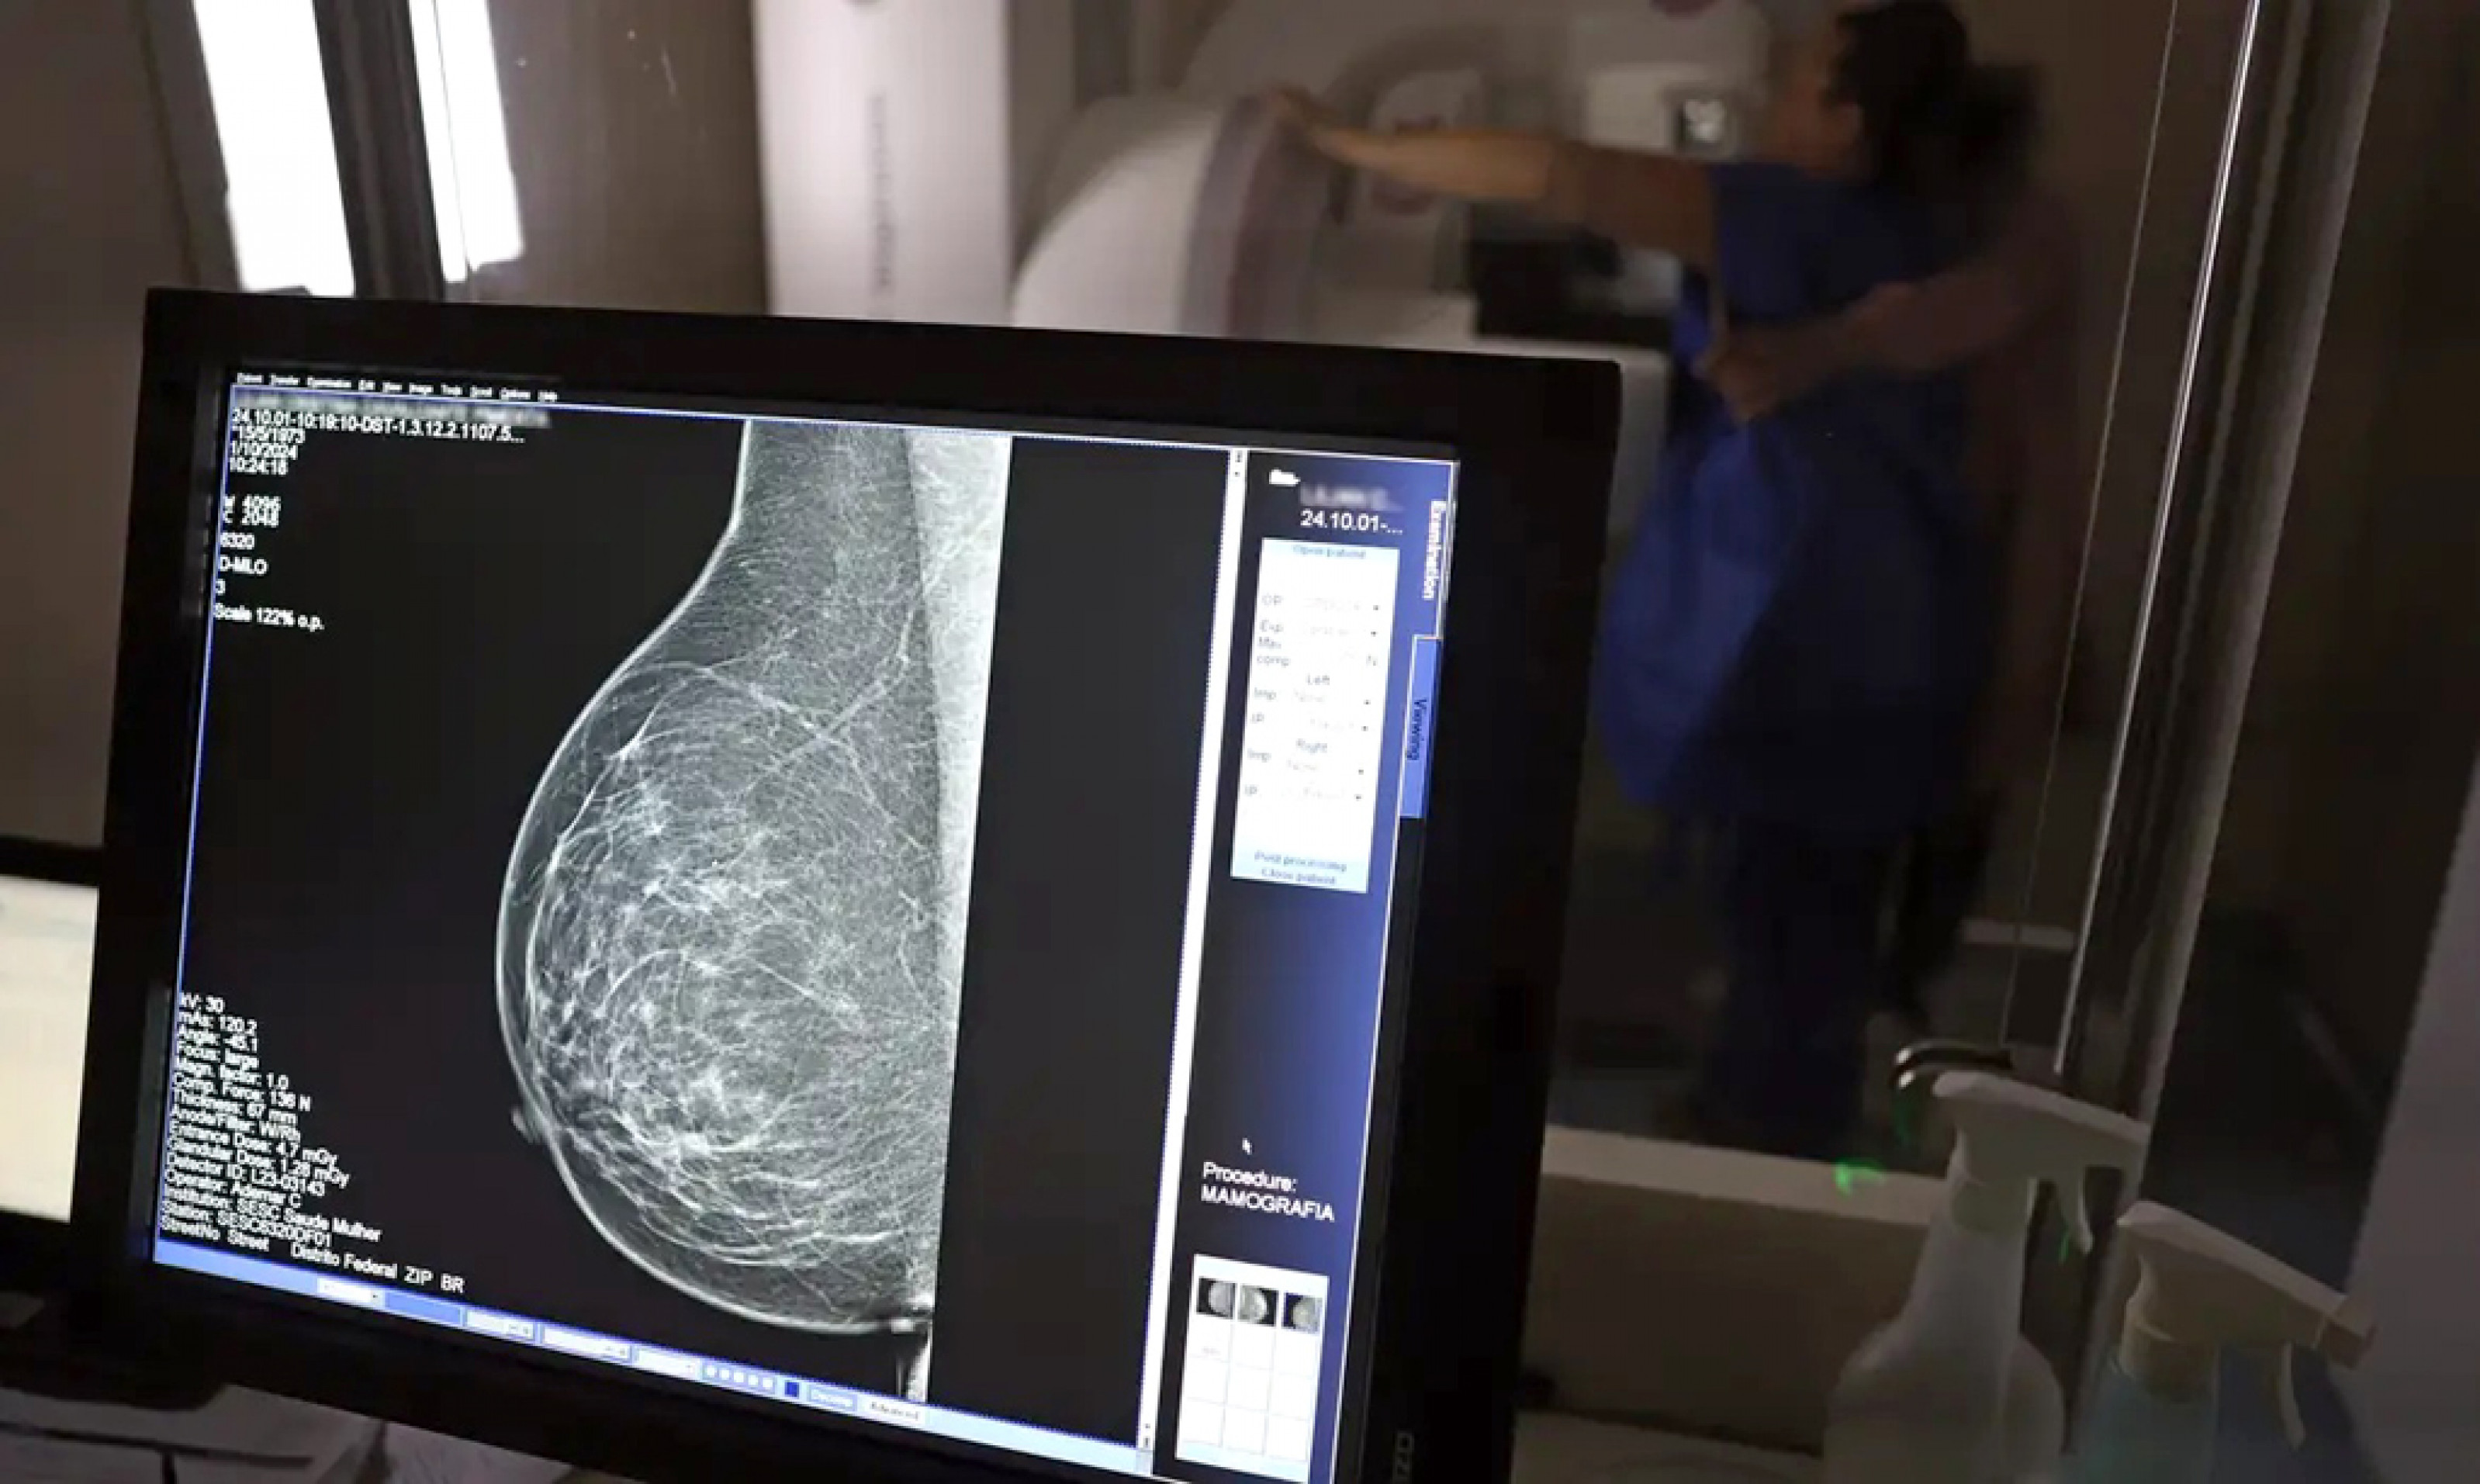

Estudo alerta para o crescimento de casos no País (Crédito: DIVULGAÇÃO)

Dados do Painel Oncologia Brasil, analisados pelo Colégio Brasileiro de Radiologia e Diagnóstico por Imagem (CBR), indicam que mais de 108 mil mulheres com menos de 50 anos foram diagnosticadas com câncer de mama no Brasil no período entre 2018 e 2023, uma média de uma em três mulheres diagnosticadas com a doença.

Para a entidade, os números reforçam a importância de ampliar o rastreamento do câncer de mama por meio da realização de mamografia em mulheres abaixo dos 50 anos e acima dos 70 anos, faixas etárias que não estão incluídas na recomendação padrão de exames preventivos no âmbito do Sistema Único de Saúde (SUS).